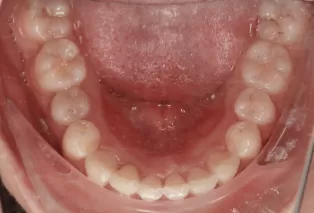

Avant le traitement

Photos intra-orales